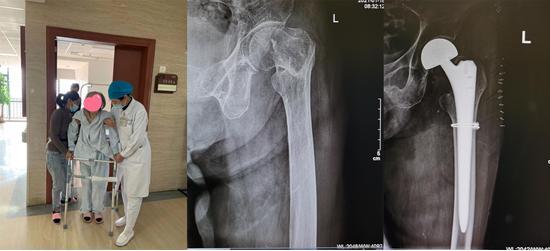

▲93岁老人和95岁老人股骨转子间粉碎性骨折,进行“半髋关节置换术+钛缆内固定”后,重新恢复行动能力

▲江奶奶进行“半髋关节置换术+钛缆内固定”后,恢复行动能力